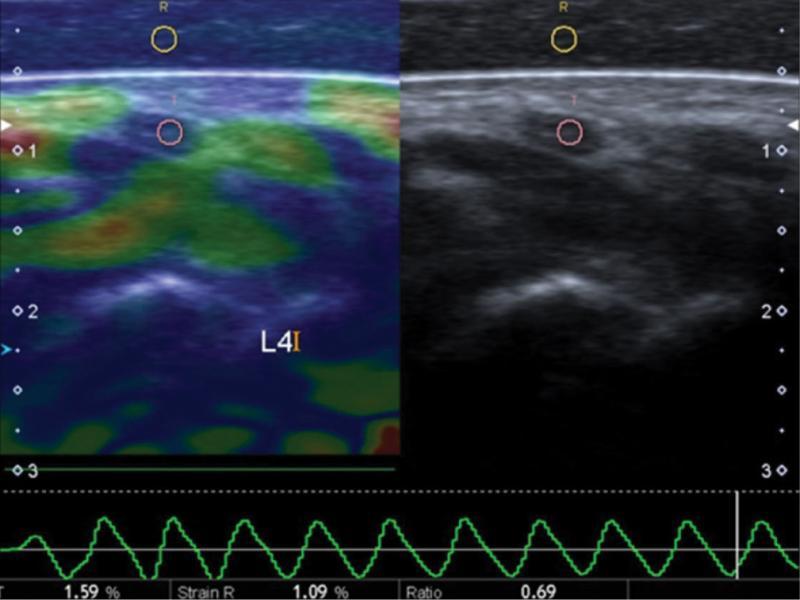

| SP/MN SI | 0.83 (0.33,1.66) | 0.69 (0.31,1.17) | 0.03 |